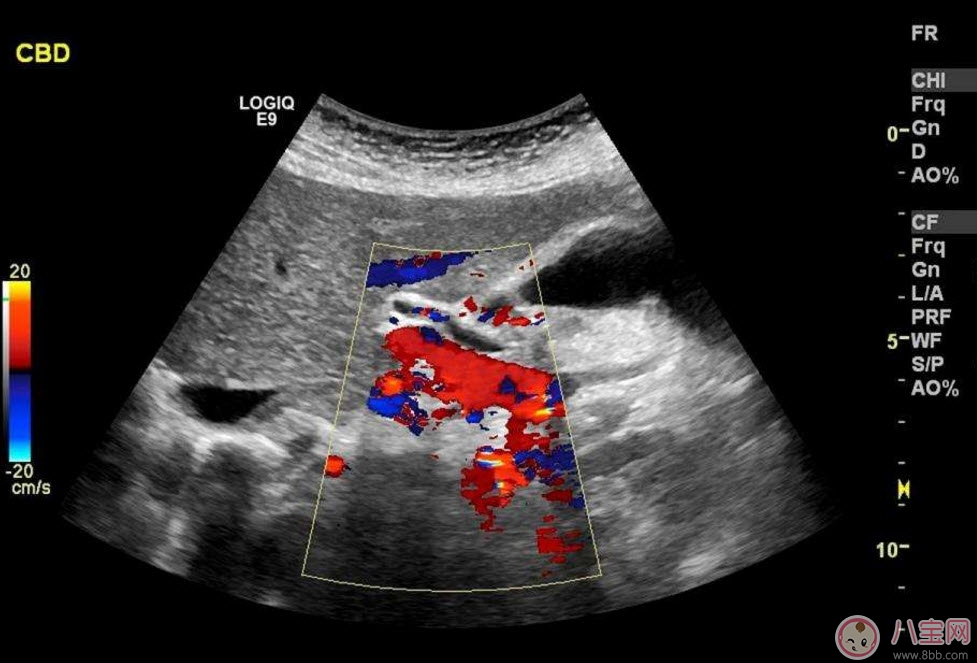

什么时候选择彩超一般在孕中期第一次排畸的时候使用 。主要是筛查胎儿各个器官是否畸形(面部及口唇除外) 。第一次筛查大概是在22-24周,排查严重的、明显的畸形,如果孕妈妈非常的胖,建议在26周左右再去做彩超 。

专家建议一般无高危等因素或其他合并症的孕妇妊娠期做彩色多普勒超声或三维超声,最好选择在孕18~24周,因为这次检查最为重要,若经济能力许可,选择分辨率高的超声仪器检查,对胎儿生长发育的观察效果当然更有帮助 。即便如此,三维或四维的超声检查与其他检查一样并非万能,不能代替其他的产前检查方法 。